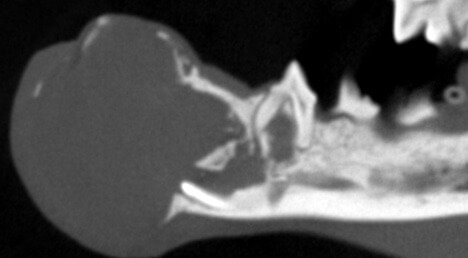

Bilateral rostral mandibulectomy to excise an oral mass that is suspected to be benign (not spreading) but locally invasive. Oral surgical removal of unerupted/impacted lower left canine tooth occupying the majority of the left mandible.

Cystic rostral mandibular swelling associated with unerupted 304. Adopted in Sept as intact male, estimate age 2. RDVM neutered and found mild swelling and unerupted 304 (lower left canine tooth). Swelling increased since adoption.

The canine tooth was not missing, but was impacted present in the middle of the left mandible. A tumor was present requiring removal of the tumor and associated impacted tooth.

We scaled, polished, performed 3D imaging and intraoral radiographs (x-rays), and confirmed the presence of an oral mass. The mass effect appears to have enlarged and extended to the lower right canine tooth.

As previously noted, the lower left canine tooth was unerupted and impacted into the center of the mandible. The cyst growth/mass effect has caused haphazard tissues to be present around all of the incisors.